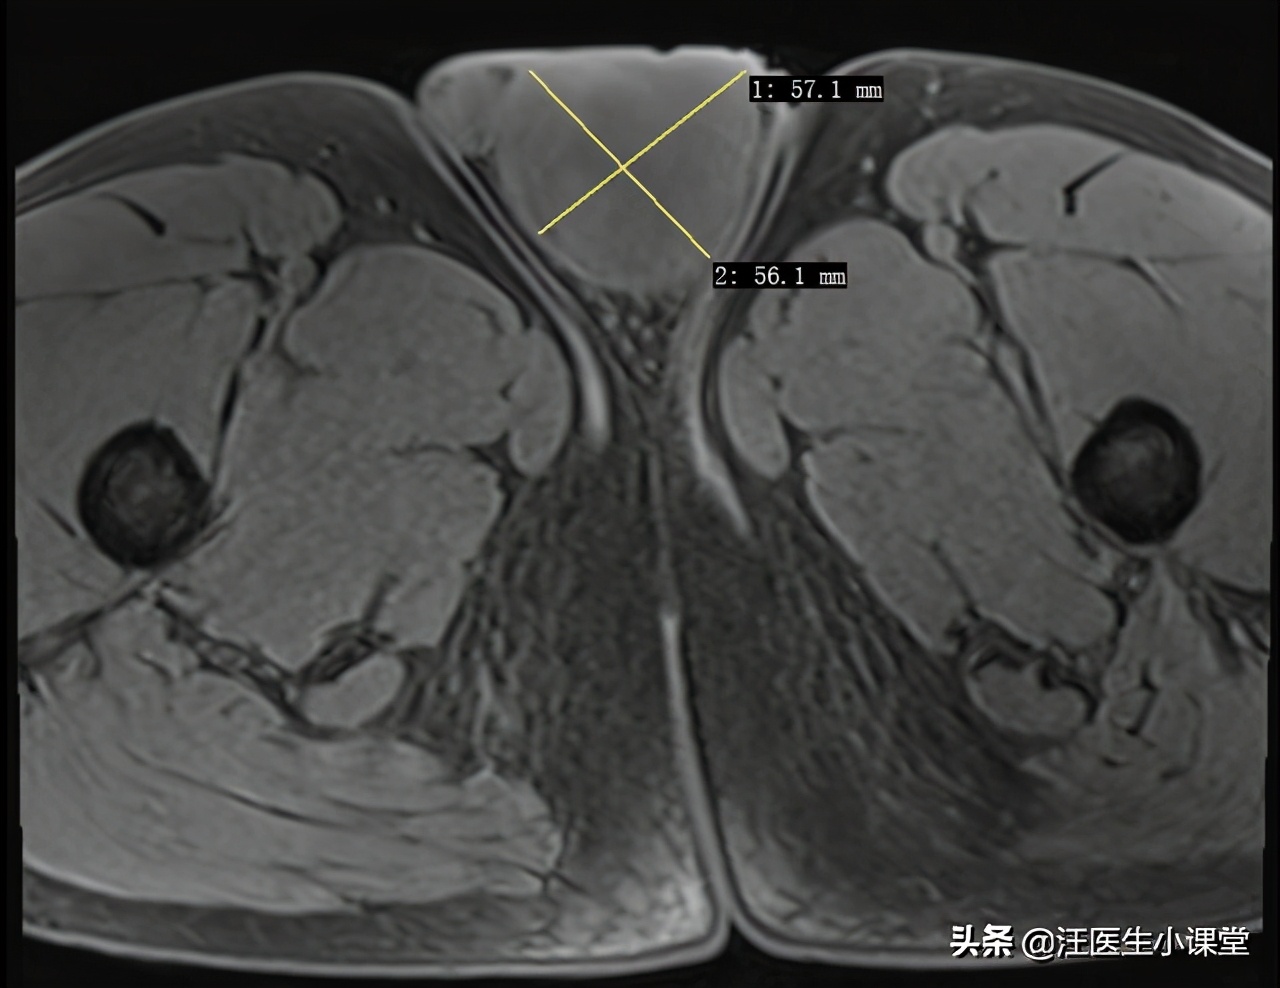

再回到我们上面说的这个小伙,通过体格检查和阴囊彩超的结果,我们初步判断其是*丸睾**肿瘤,*丸睾**肿瘤大多是恶性,不是很常见,大约占男性肿瘤的1%,好发于中青年。为了进一步明确诊断及判断其有无淋巴结受累,我们给他做了盆腔核磁,核磁共振在诊断的敏感性和特异性方面优于彩超,且更适合软组织的检查。我们下面来看看他的阴囊核磁结果。

阴囊MRI显示左侧肿物

阴囊MRI首先考虑精原细胞瘤

阴囊核磁检查首先考虑为精原细胞瘤,这种肿瘤是青少年男性最常见的*丸睾**肿瘤,精原细胞和间质细胞以及支持细胞一起组成*丸睾**,因为精原细胞复制活跃,也更容易发生癌变,精原细胞瘤主要通过外科手术治疗,也就是要把患侧*丸睾**和肿瘤彻底切除,配合术后的放化疗,临床治愈率还是比较高的。可惜很多人没有认识到尽早治疗的重要性,就像这个小伙子前前后后拖延了3个月,如果肿瘤发生转移了那么治疗起来就很麻烦了,预后也不好。今天和大家分享这个病例,也是希望给那些有类似疾病的患者一个提醒,对于肿瘤一定要在它早期的时候切掉它!!!